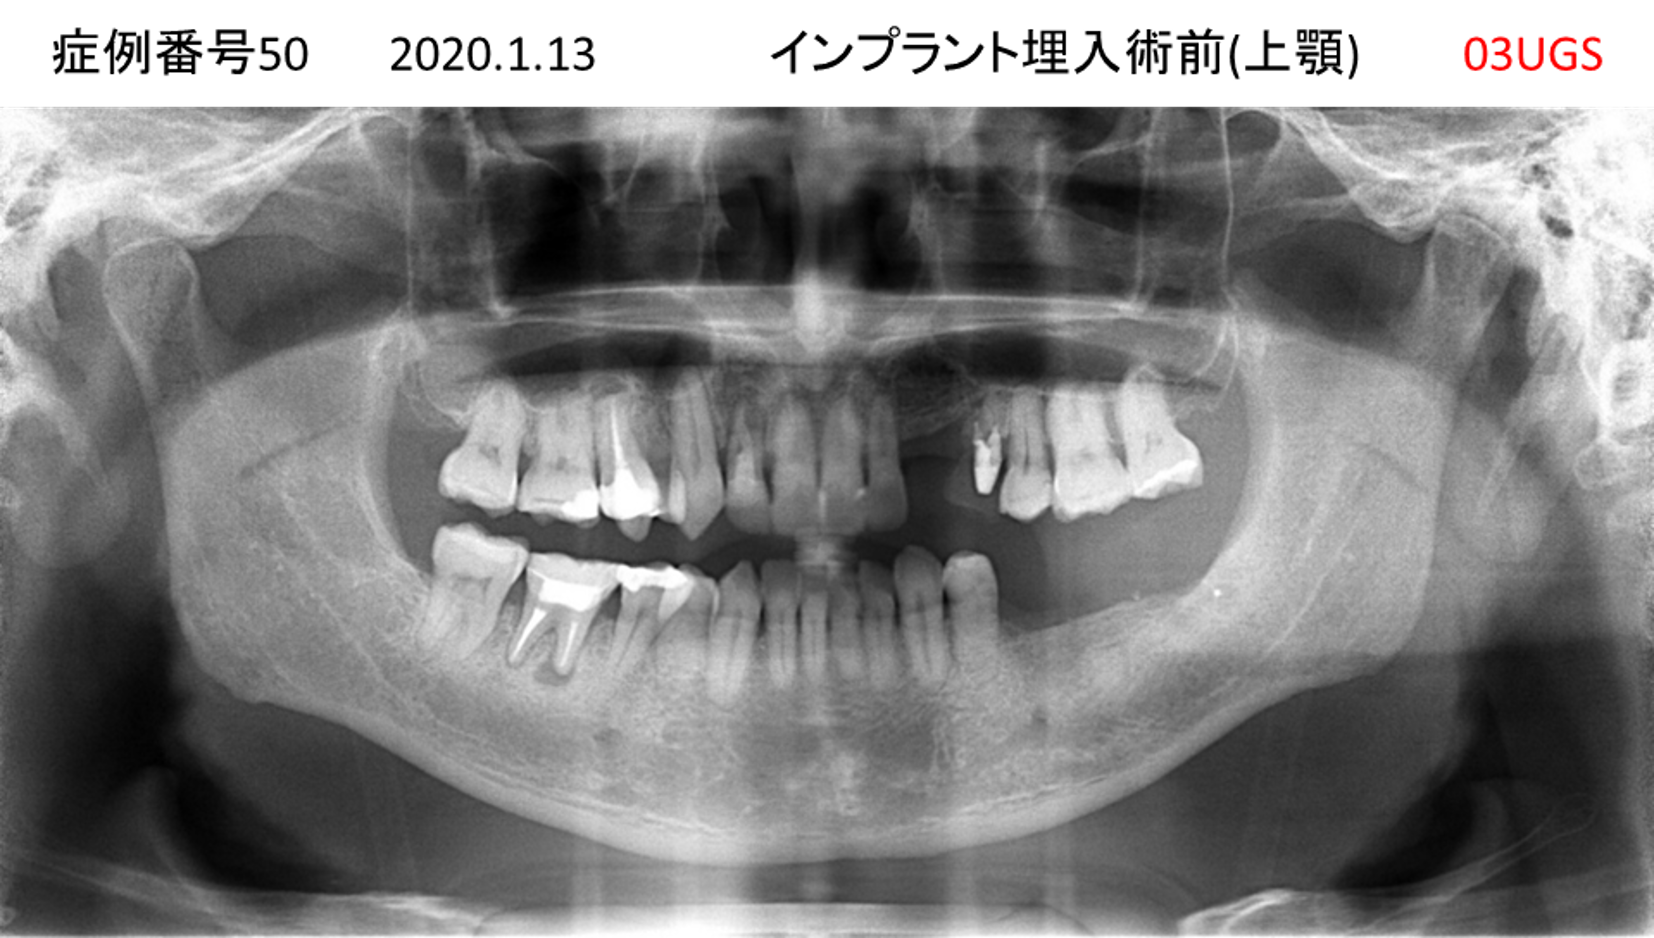

上の前歯が揺れてきてかめない患者様のインプラント症例

| 治療名称 |

インプラント |

| 治療費用 |

335万円+税 |

| 治療期間 |

4か月 |

| 患者さんの症状(主訴) |

上の前歯が揺れてきて噛めない |

| 治療内容 |

サイナスリフト 抜歯即時インプラント |

| 治療結果 |

ちゃんと噛めるようになった。不安がなくなった。見た目がとても良くなったのすごくうれしい。 |

| 治療の注意点(リスク/副作用) |

インプラントが壊れたら再治療が必要 |